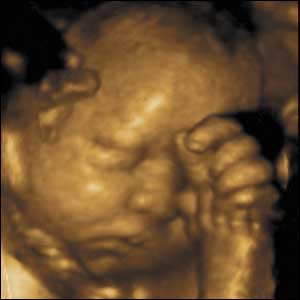

انظري اليه في الاسبوع ال38

وهذه صور أجنة توأم عبر جهاز موجات فوق الصوتية :